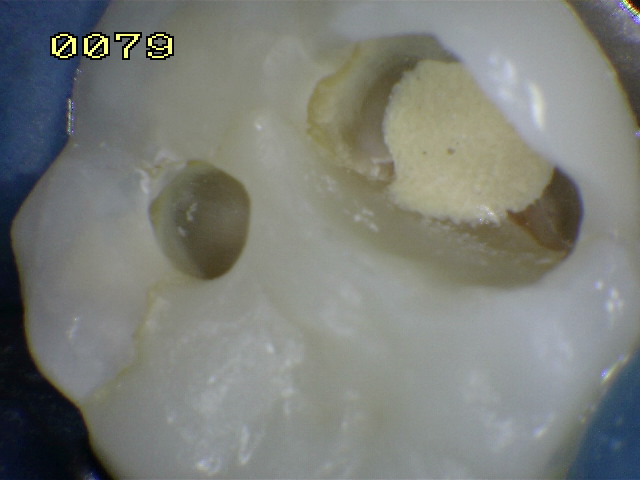

La flecha amarilla indica un posible cuarto conducto.

Observe el remanente de esmalte en la ángulo axio gingival de la cavidad y la desadaptación de la matriz metálica